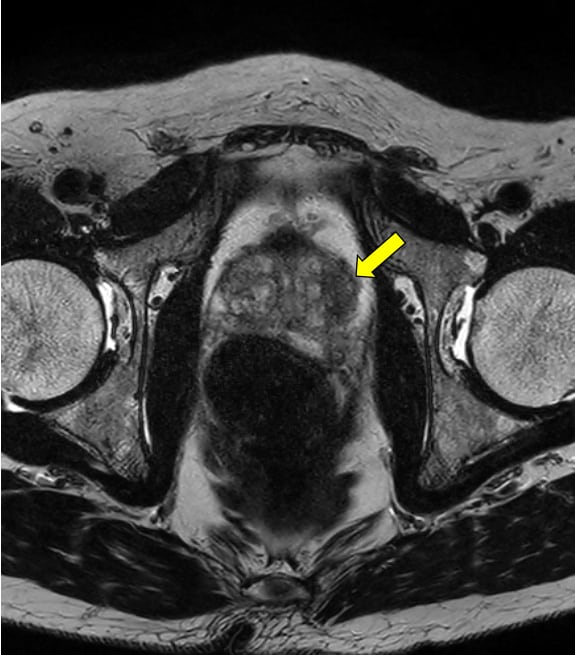

本症例ではPSA高値を契機に前立腺MRI検査を施行した。便秘症があるため、直腸は拡張し、内部にガスを含む便塊を認める。鎮痙薬は、既往症のため、使用せず、検査前の排便も不可能であったために、画質劣化が避けられない。腸管ガスによるひずみの影響で、全ての撮像シーケンスで、前立腺の後方の辺縁は不鮮明で、内部の信号が不均一となる。特に空気や蠕動の影響を受けやすい、拡散強調画像での画質劣化が著しい。

拡散強調画像(DWI)では、腸管ガスによるひずみの影響を減らすため、echo planar imaging(EPI)を用いたDWIよりTurbo spin echo(TSE)を用いたDWIを使用する。high b valueの画像は、computed DWIで作成することで、実際の撮像よりもノイズを低減できる場合がある。また、ダイナミック造影MRIを追加すると、短時間撮影のため前立腺の輪郭も明瞭で、癌部と非癌部のコントラストがつき、病変の検出に役立つ場合がある。